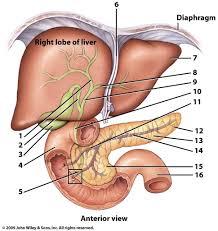

(Common) Hepatic Duct

Celiac trunk

Common bile duct

Common hepatic artery

Cystic duct

Gall bladder

Hepatic portal vein

Left gastric artery/vein

Liver

Pancreas

Pancreatic duct

Splenic artery/vein